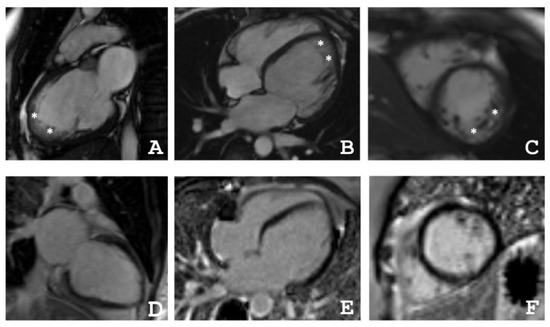

4.2. Cardiac Magnetic Resonance Imaging

| Patient | The Ratio NC/C in Segments | ||||||||||||||||

|---|---|---|---|---|---|---|---|---|---|---|---|---|---|---|---|---|---|

| 1 | 2 | 3 | 4 | 5 | 6 | 7 | 8 | 9 | 10 | 11 | 12 | 13 | 14 | 15 | 16 | 17 | |

| III-2 | 0 | 0 | 0 | 0 | 0 | 1.1 | 4.0 | 0 | 0 | 1.6 | 2.1 | 3.5 | 0 | 0 | 1.4 | 0 | 0 |

| III-4 | 1.2 | 0 | 0 | 0 | 1.2 | 2.2 | 1.1 | 0 | 0 | 3.8 | 3.0 | 3.0 | 4.9 | 3.3 | 3.5 | 2.8 | 5.9 |

| IV-3 | 3.3 | 1 | 0 | 0 | 0 | 0 | 3.5 | 2.5 | 1.1 | 0 | 0 | 1 | 8.3 | 8.3 | 6.3 | 8.3 | 10.5 |

| Patient | EDV | EF | Grothoff, [16] | Jacquier, % [17] | Petersen, [18] | |||

|---|---|---|---|---|---|---|---|---|

| Mass Index of NC, g/m² | NC/Myocardial mass, % | NC/C ≥ 3:1 in One Segment(1–3, 7–16) | NC/C ≥ 2:1 in 4–6th Segments | |||||

| III-2 | 77 | 31 | 12 | 20 | + | − | 20 | + |

| III-4 | 82 | 55 | 8 | 14 | + | + | 16 | + |

| IV-3 | 64 | 48 | 21 | 36 | + | − | 36 | + |